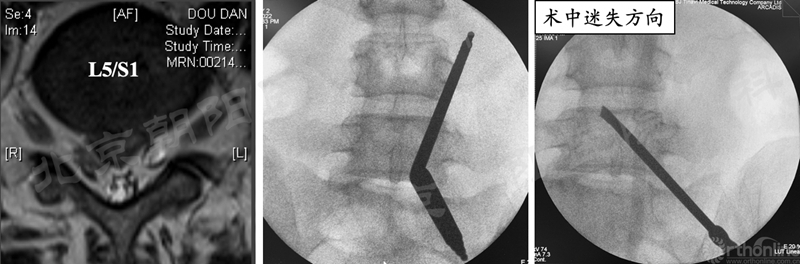

2、 镜下迷失——节段错误

#14例UBE,术中迷路,L5/S1突出做到了L4/5(右侧透视图),及时转开放减压。

本例手术镜下迷失原因总结:

① 术前设计切口靠近端,本期望利于椎板钳减压椎板,弄巧成拙;

② 定位后通道方向没有记牢,操作时角度改变了;

③ 做L5/S1体位摆放应注意把上半身摇高,使L5/S1水平;

④ 透视正位应将L5/S1间隙标准化,否则定位不准;

⑤ 患者肥胖,脂肪软组织厚;

⑥ 镜下结构不对马上透视。